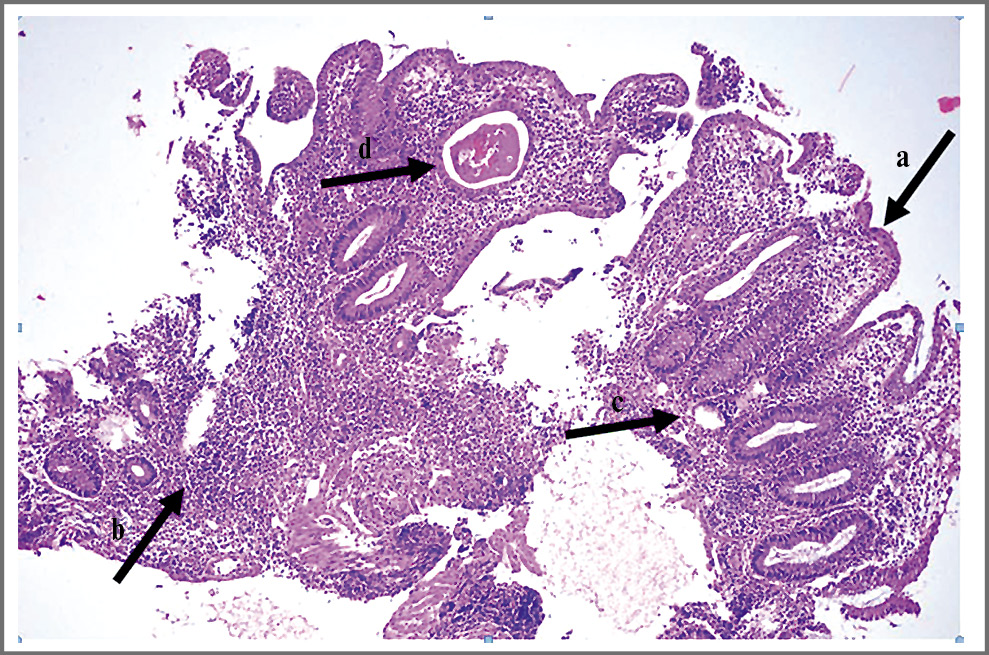

Анализы крови: гемоглобин (Нb) – 99 г/л, эритроциты – 3,46×1012/л, гематокрит – 30,2%, MCV (средний объем эритроцитов) – 87 фл, MCH (содержание гемоглобина в эритроцитах) – 28,5 пг, тромбоциты – 576×109/л, лейкоциты – 8,3×109/л, нейтрофилы – 44,5%, лимфоциты – 39,7%, моноциты – 12,5%, эозинофилы – 2,2%, базофилы – 1,1%; С-реактивный белок (СРБ) – 199,51 (норма ≤5,00) мг/л, фибриноген – 6,1 (норма 2,76–4,71) г/л, D-димер – 1196 (норма 0–243) нг/мл, РСТ (прокальцитонин) – 0 (норма ≤0,5) нг/мл, общий белок – 66,6 (норма 57,0–82,0) г/л, ревматоидный фактор – 7,6 (норма ≤14,0) МЕ/мл. В динамике: СРБ – 257,05 мг/л, общий белок – 52,4 г/л, альбумин – 21,5 (норма 35,0–52,0) г/л. Спиральная КТ придаточных пазух носа: КТ-признаки пристеночного утолщения слизистой основной пазухи. Рентгенография левой стопы в одной проекции: костно-травматических и деструктивных изменений не выявлено; вальгусная деформация I пальца; деформирующий артроз 1-го плюснефалангового сустава. Эзофагогастродуоденоскопия: атрофический гастрит; хроническая эрозия препилорического отдела желудка. Колоноскопия: при визуальном осмотре перианальной области изменений не выявлено. В области ануса определяются внутренние геморроидальные узлы, умеренно напряженные, без признаков воспаления, венозный сосудистый рисунок отсутствует. Слизистая матовая, сосудистый рисунок смазан, местами не визуализируется, определяются полигональные продольные крипто-абсцессы. Аппарат проведен до средней трети восходящей ободочной кишки. В просвете осмотренных отделов ободочной кишки – обильное количество промывной жидкости бурого цвета с фрагментами сгустков измененной крови. В проекции средней трети восходящей ободочной кишки и от уровня нижней трети сигмовидной кишки до средней трети нисходящей ободочной кишки определяется сегментарное поражение толстой кишки с циркулярным изменением слизистой на протяжении. Форма просвета на пораженных участках не соответствует осмотренным отделам, расправляется при инсуфляции, складки на пораженных участках местами отсутствуют, создавая вид трубки, местами выраженно отечные, тонус кишки снижен. Перистальтика отсутствует. Слизистая отечна, инфильтрирована, имеет цвет различных оттенков красного и бурого, поверхность шероховатая, покрыта слизью, сосудистый рисунок не дифференцируется. В нижней трети нисходящей ободочной и сигмовидной кишки и видимой части восходящей ободочной кишки определяются множественные обширные изъязвления неправильной формы, площадь эрозированной поверхности увеличена за счет сливных язв и эрозий неправильной формы, напоминает «географическую карту» с вкраплениями «глыбок» грануляционной ткани и псевдополипов неправильной формы, размером 3–9 мм. Выполнена биопсия. Отмечается умеренная контактная кровоточивость. Заключение: субтотальный ЯК 3-й степени, выраженная степень активности (по D. Rachmilewitz); состоявшееся кишечное кровотечение; хронический внутренний геморрой вне обострения. При морфологическом исследовании биоптатов выявлены язвенные дефекты слизистой оболочки толстой кишки до мышечного слоя, смешанно-клеточная воспалительная инфильтрация (рис. 1, 2). При посеве содержимого абсцесса носовой перегородки и раневого отделяемого из области флегмоны левой стопы роста микрофлоры не получено. Посев крови из вены: проба стерильна.

Рис. 1. Фрагмент слизистой оболочки толстой кишки с очаговым некрозом поверхностного эпителия. Покровный эпителий частично представлен незрелыми регенерирующими эпителиоцитами, лишенными муцина (a). Плотный инфильтрат, состоящий из лимфоцитов и плазматических клеток, нейтрофильных лейкоцитов в пределах слизистой оболочки (b) и поверхностных отделах подслизистого слоя; наличие небольших эрозий меду криптами (c). Железы с кистозным расширением (d) и наличием в просвете гомогенного содержимого с примесью лейкоцитов; формирование крипт-абсцессов. Окраска гематоксилином и эозином ×200.